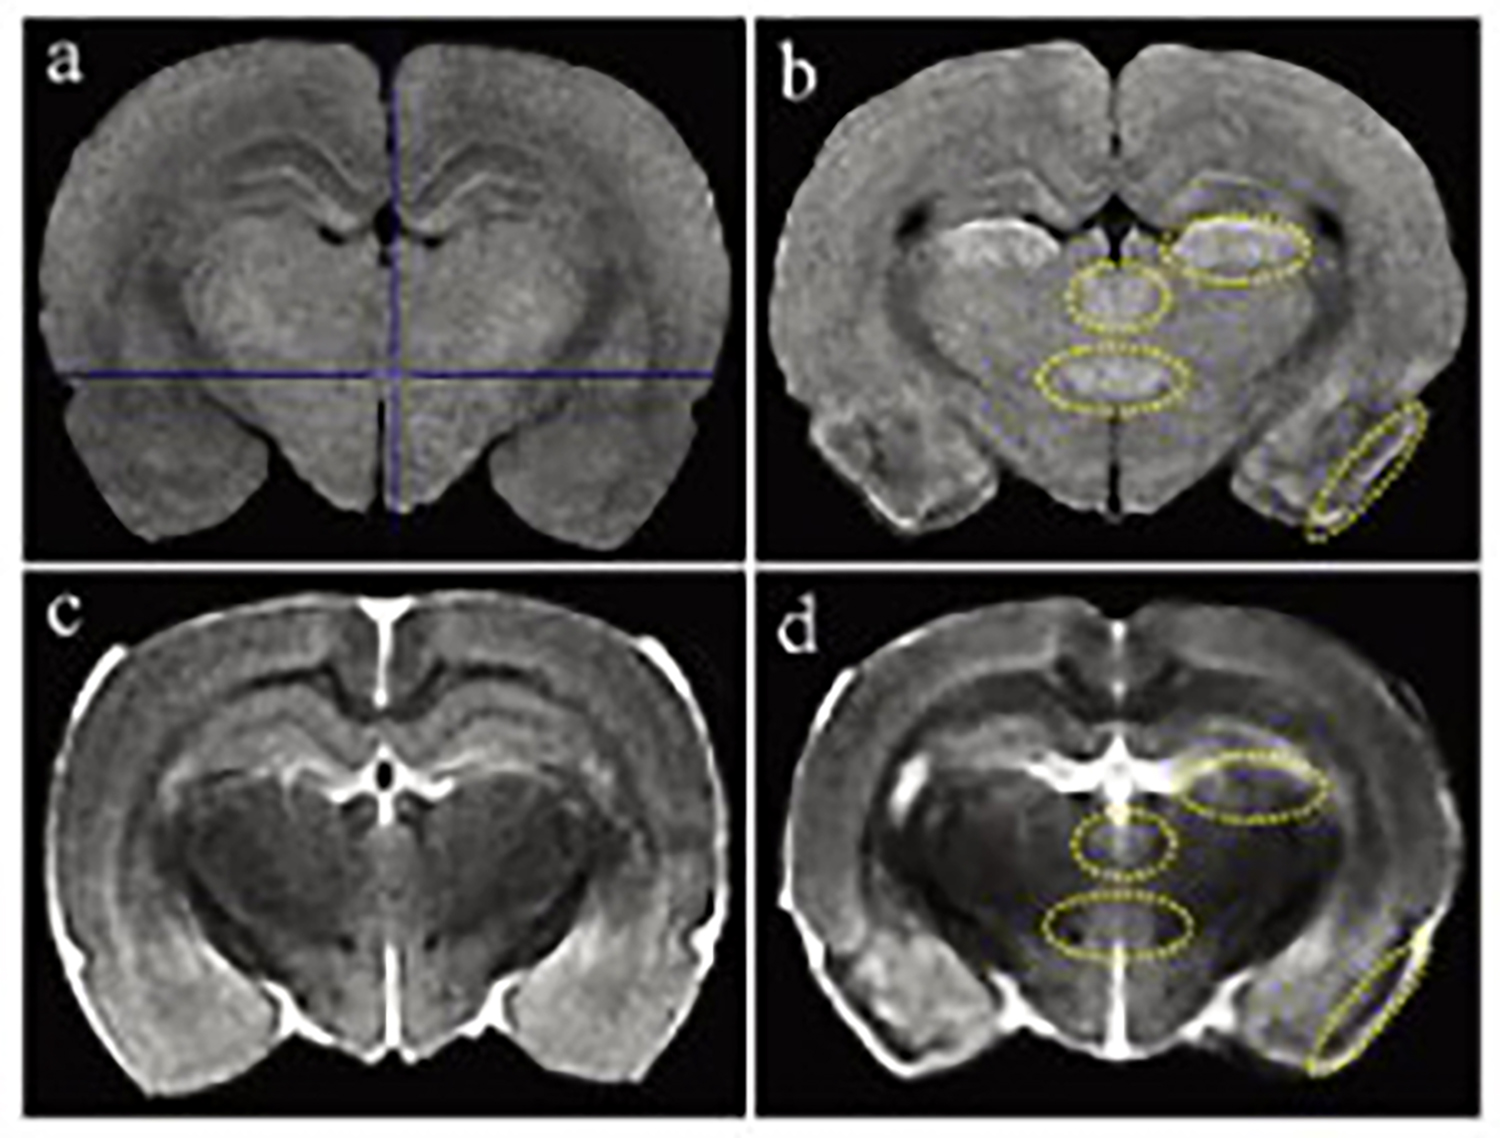

基于MRI(1T)的小鼠生理特征定量计算

磁共振成像(MRI)广泛应用于临床前研究和药物开发,是一种强有力的无创性方法,可用于评估小鼠疾病模型的表型和治疗效果。

一个新的紧凑型高性能小动物磁共振成像平台(M3),该系统使用一种新的磁铁设计和一套相关的软件,降低了小动物磁共振成像仪的成本和复杂性。